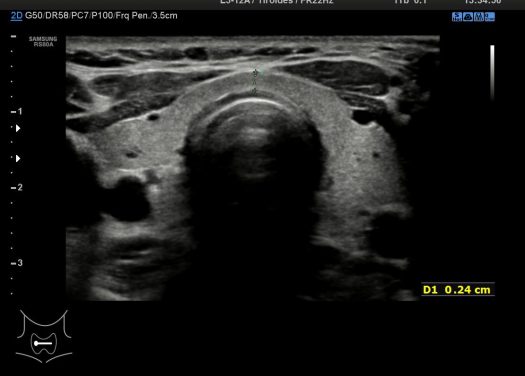

3. Medida Istmo

Imagen 3 donde observamos el Istmo y hacemos medida para evaluar un posible aumento de la glándula, no debe superar esta medida en AP los 0,3 cms.

Image 3 where we observe the Isthmus and measure to evaluate a possible increase in the gland, this measure should not exceed 0.3 cm in AP.